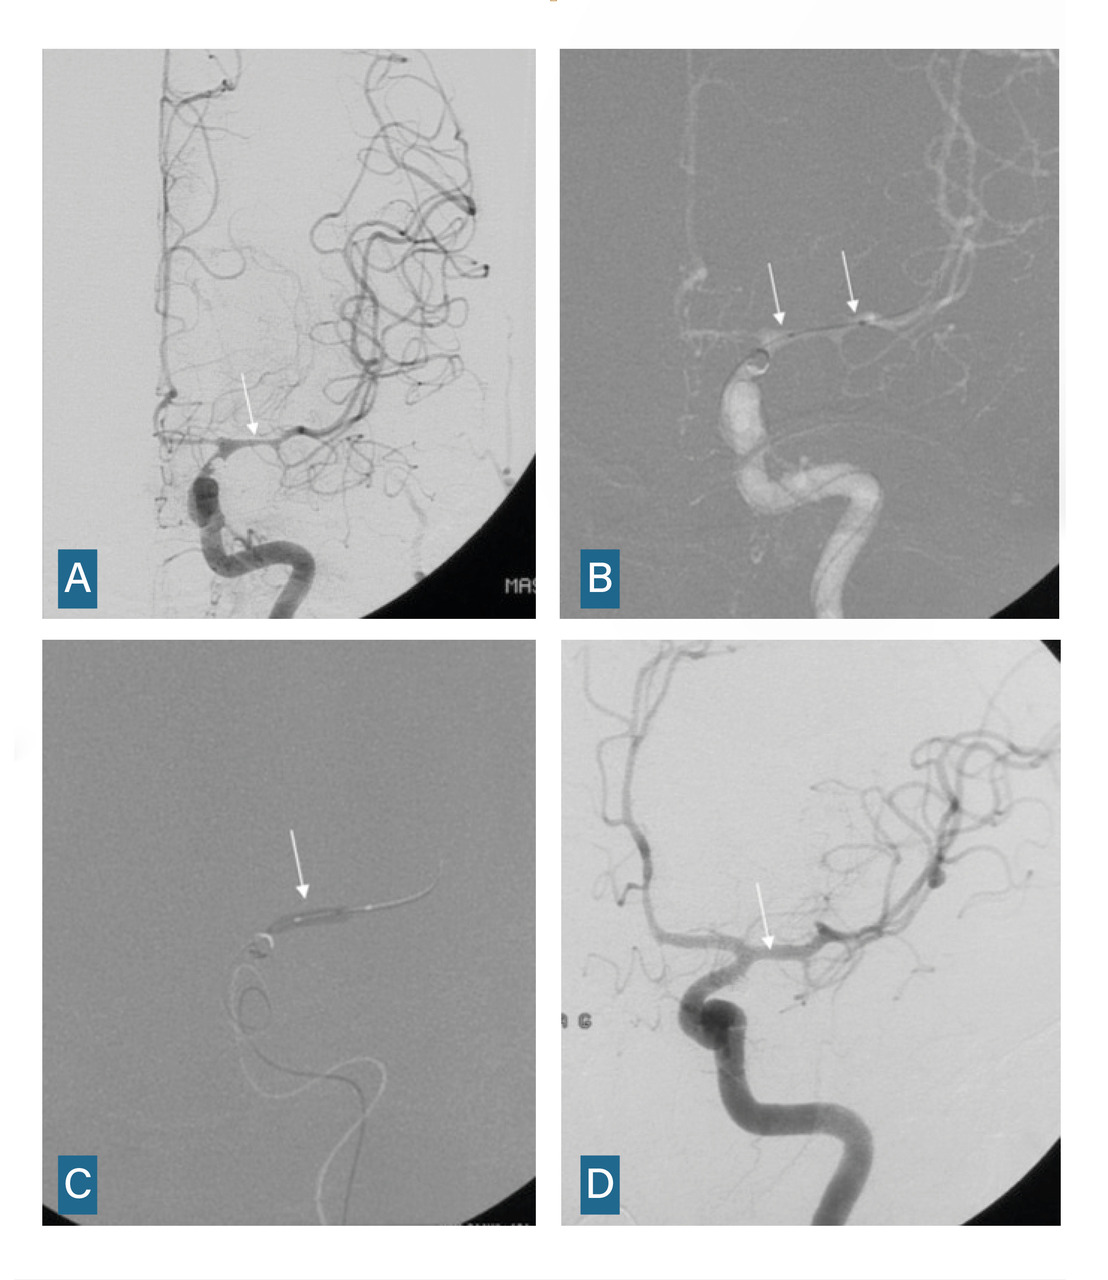

L’angiographie digitale permet de planifier et de suivre le traitement lorsqu’il est réalisé par voie endovasculaire. (fig. 4)